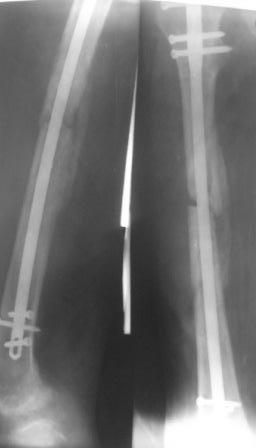

> Уважаемые коллеги, может быть лучше использовать спейсер с

> антибиотиками (но у нас нет костного цемента), или другие варианты

> лечения? Р-снимок прилагается.

Однако мозоль формируется.

Ждать...